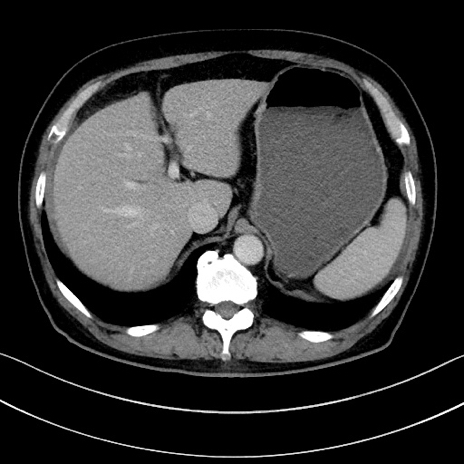

冠状断像

【症例】70歳代男性

【主訴】腹痛

【現病歴】今朝から腹痛あり。全体的に痛い。特に左上の方。排ガスが今日はない。冷や汗が出る。

【既往歴】直腸癌術後

【身体所見】左側腹部〜上腹部に圧痛あり。腹膜刺激症状明らかなではない。軽度反跳痛。左下腹部に術後瘢痕あり。

【データ】WBC 7700、CRP 0.02